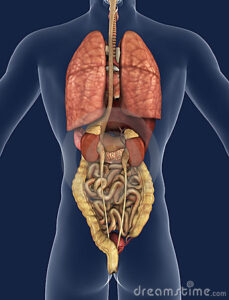

Organi e organismo.

“Ogni organo manifesta una duplice natura: da una parte è una formazione chiusa, che nella sua specificità isola nettamente dal restante organismo, dall’altra parte è aperto ai processi dell’intero organismo.”

Immagine dal libro: la relazione degli organi con il sangue arterioso – rosso, e venoso – blu, crea quattro “motivi d’organo”:

- Nel Polmone il sangue da blu diventa rosso

- Nel Fegato blu rimane blu

- Nel Rene rosso rimane rosso

- Nel cuore rosso contro blu